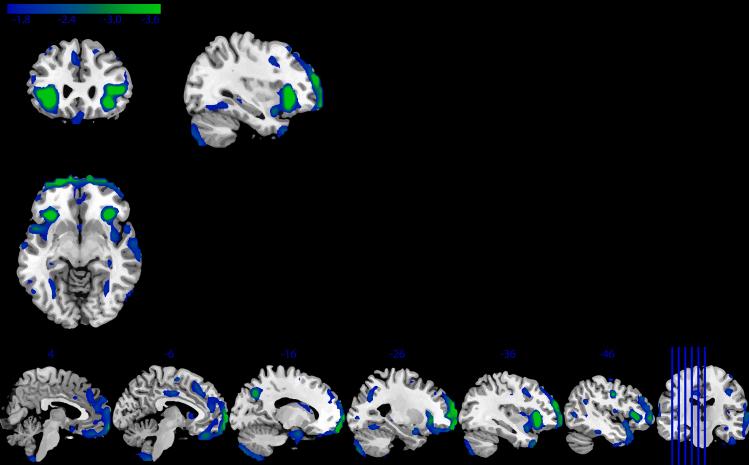

Structural neuroimaging studies have identified a combination of shared and disorder-specific patterns of gray matter (GM) deficits across psychiatric disorders. Pooling large data allows for examination of a possible common neuroanatomical basis that may identify a certain vulnerability for mental illness. Large-scale collaborative research is already facilitated by data repositories, institutionally supported databases, and data archives. However, these data-sharing methodologies can suffer from significant barriers. Federated approaches augment these approaches by enabling access or more sophisticated, shareable and scaled-up analyses of large-scale data. We examined GM alterations using Collaborative Informatics and Neuroimaging Suite Toolkit for Anonymous Computation, an open-source, decentralized analysis application. Through federated analysis of eight sites, we identified significant overlap in the GM patterns ( = 4,102) of individuals with schizophrenia, major depressive disorder, and autism spectrum disorder. These results show cortical and subcortical regions that may indicate a shared vulnerability to psychiatric disorders.

结构神经影像学研究已经确定了跨精神疾病的灰质(GM)缺陷的共享模式和特定疾病模式的组合。汇总大数据有助于检查可能的共同神经解剖学基础,这可能识别出精神疾病的某种易感性。数据存储库、机构支持的数据库和数据档案已经促进了大规模的合作研究。然而,这些数据共享方法可能存在重大障碍。联邦方法通过实现对大规模数据的访问或更复杂、可共享和可扩展的分析来增强这些方法。我们使用用于匿名计算的协作信息学和神经影像学套件工具包(一种开源、去中心化的分析应用程序)检查了灰质改变。通过对八个站点的联邦分析,我们在精神分裂症、重度抑郁症和自闭症谱系障碍患者的灰质模式(n = 4102)中发现了显著重叠。这些结果显示了可能表明对精神疾病存在共同易感性的皮质和皮质下区域。